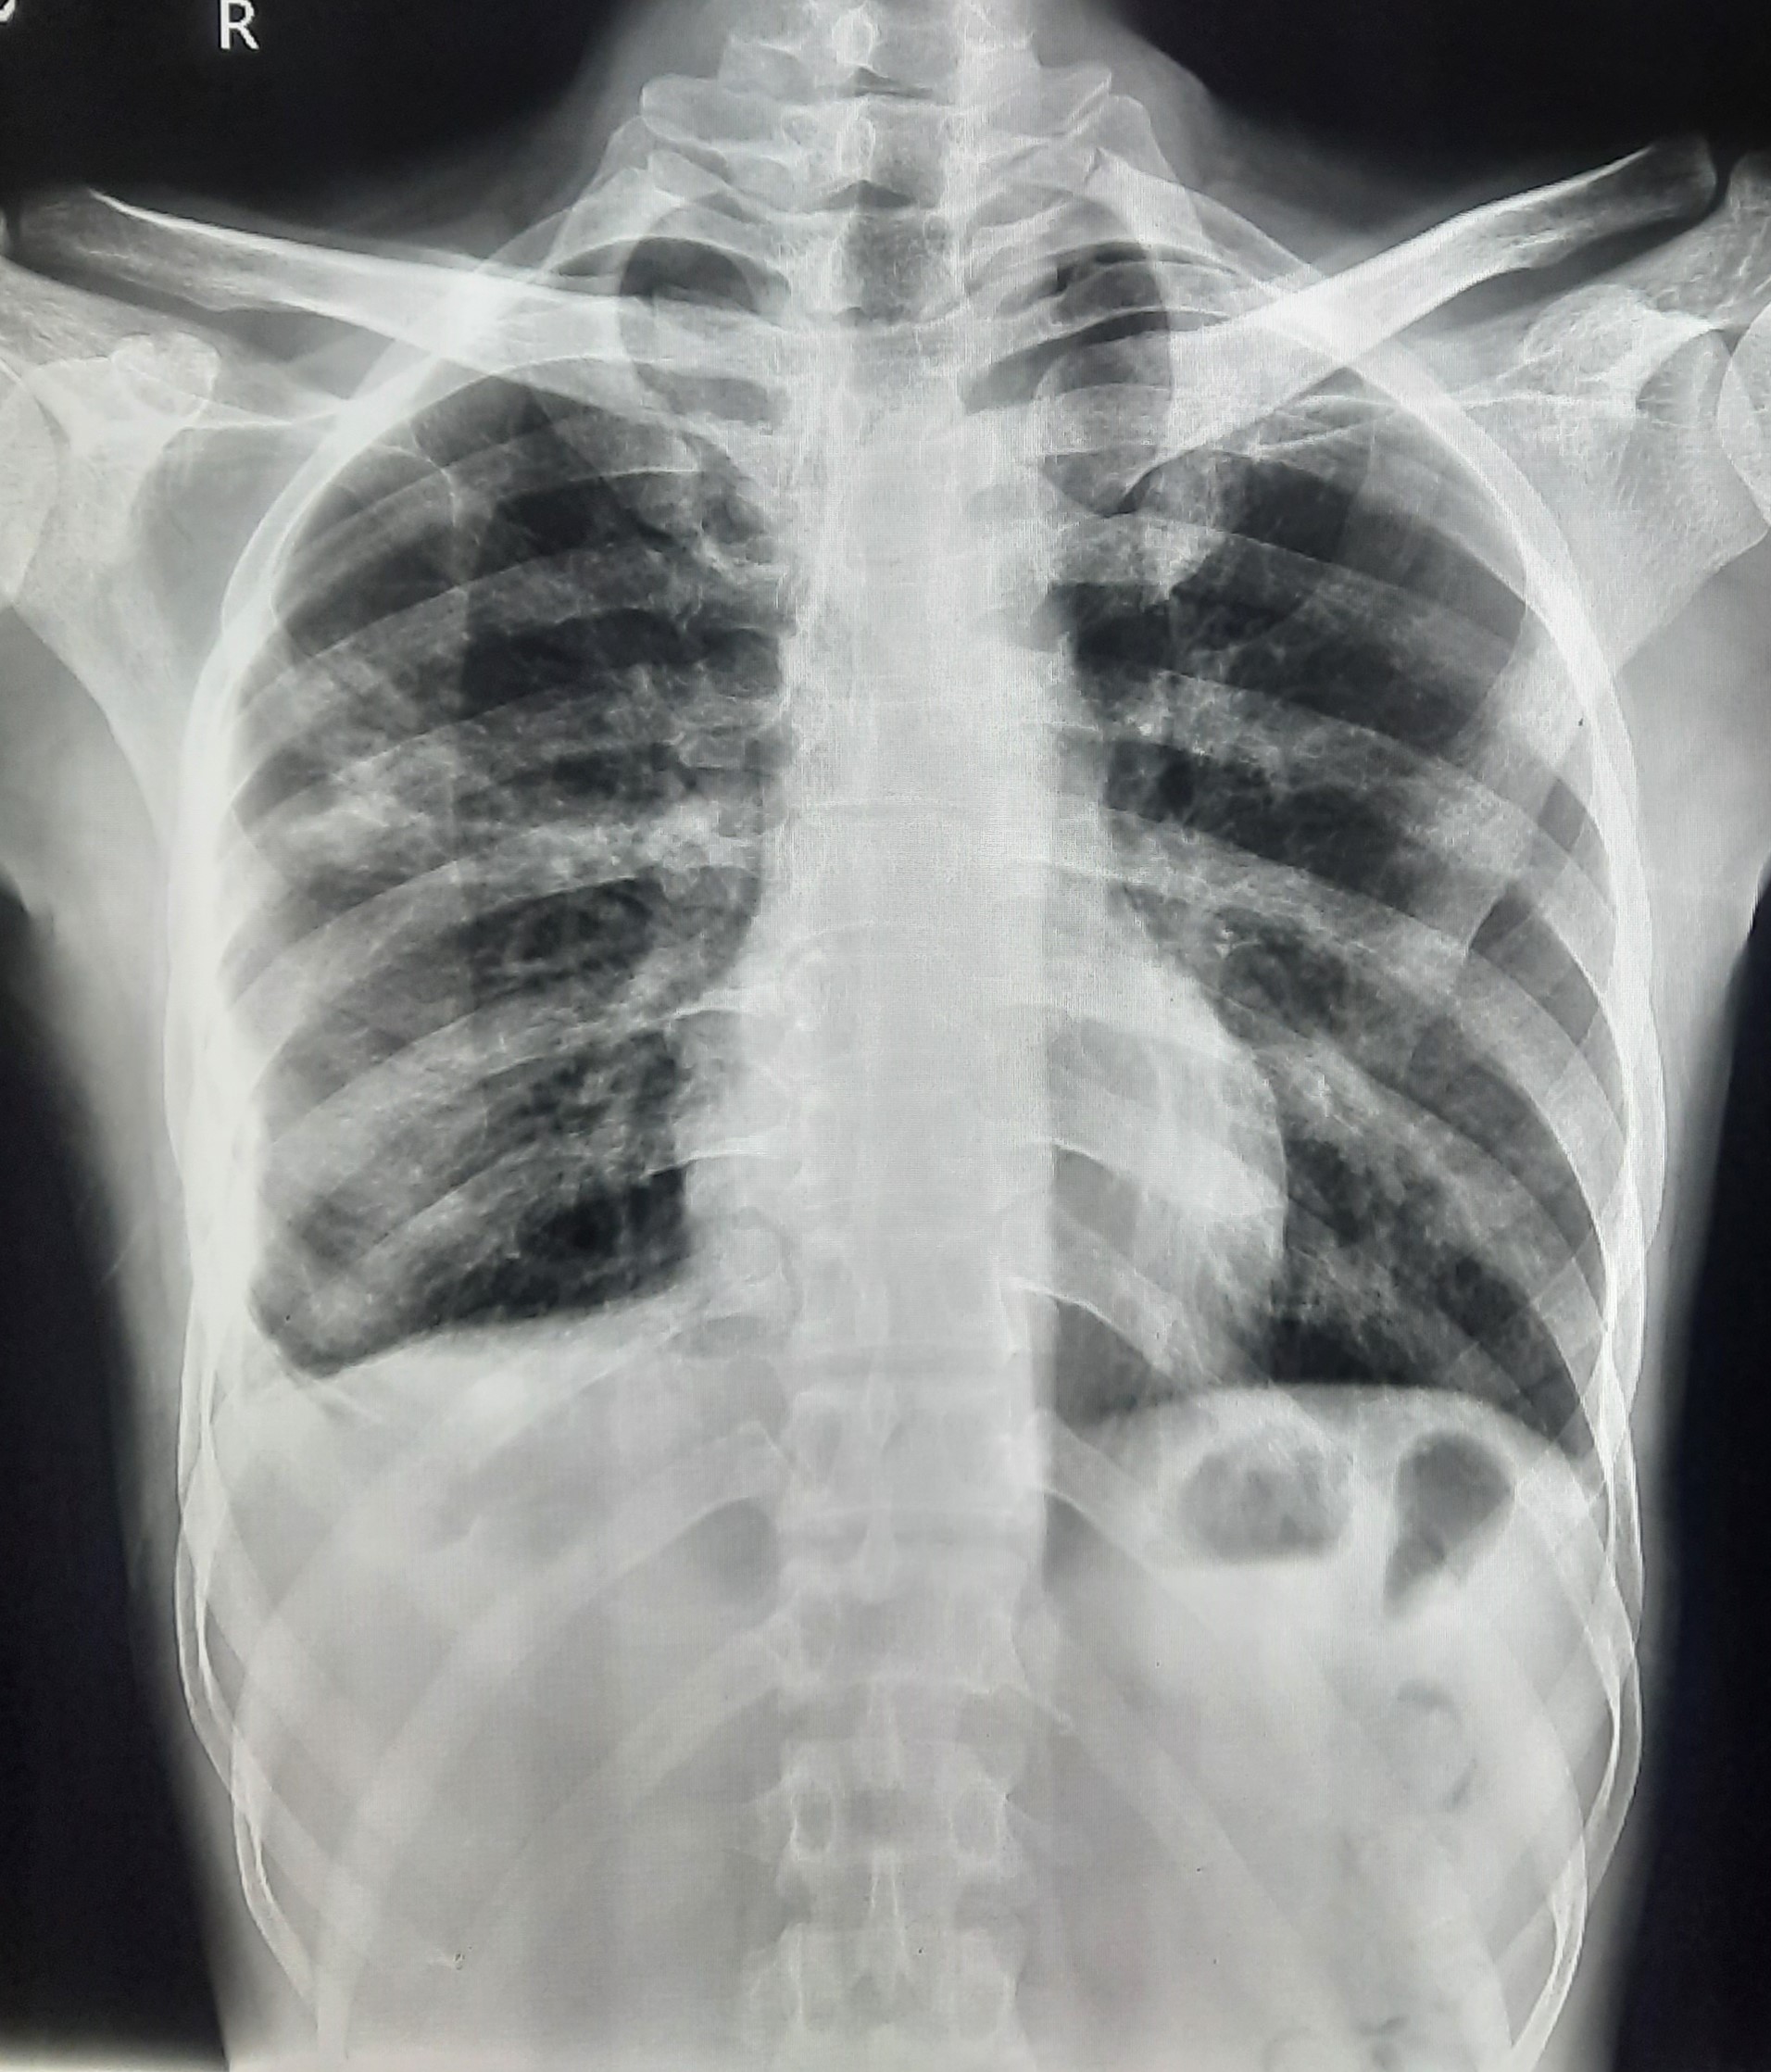

| 102 | IGGMC, Nagpur, Nagpur | P2 | 29-4370 | Prachi Bawane | Consent taken on Paper | 17 Yrs. |

Provisional Diag : PTB?

Final Diag : Active Pulmonary Tuberculosis With Tuberculi? Right Sided Pleural Effusion |

TB Case (Confirmed) | Bilateral ill Defined, No Homogenous Reticulonodular opacities, Right CP Angle Blunting | Abnormality visible on x-ray |